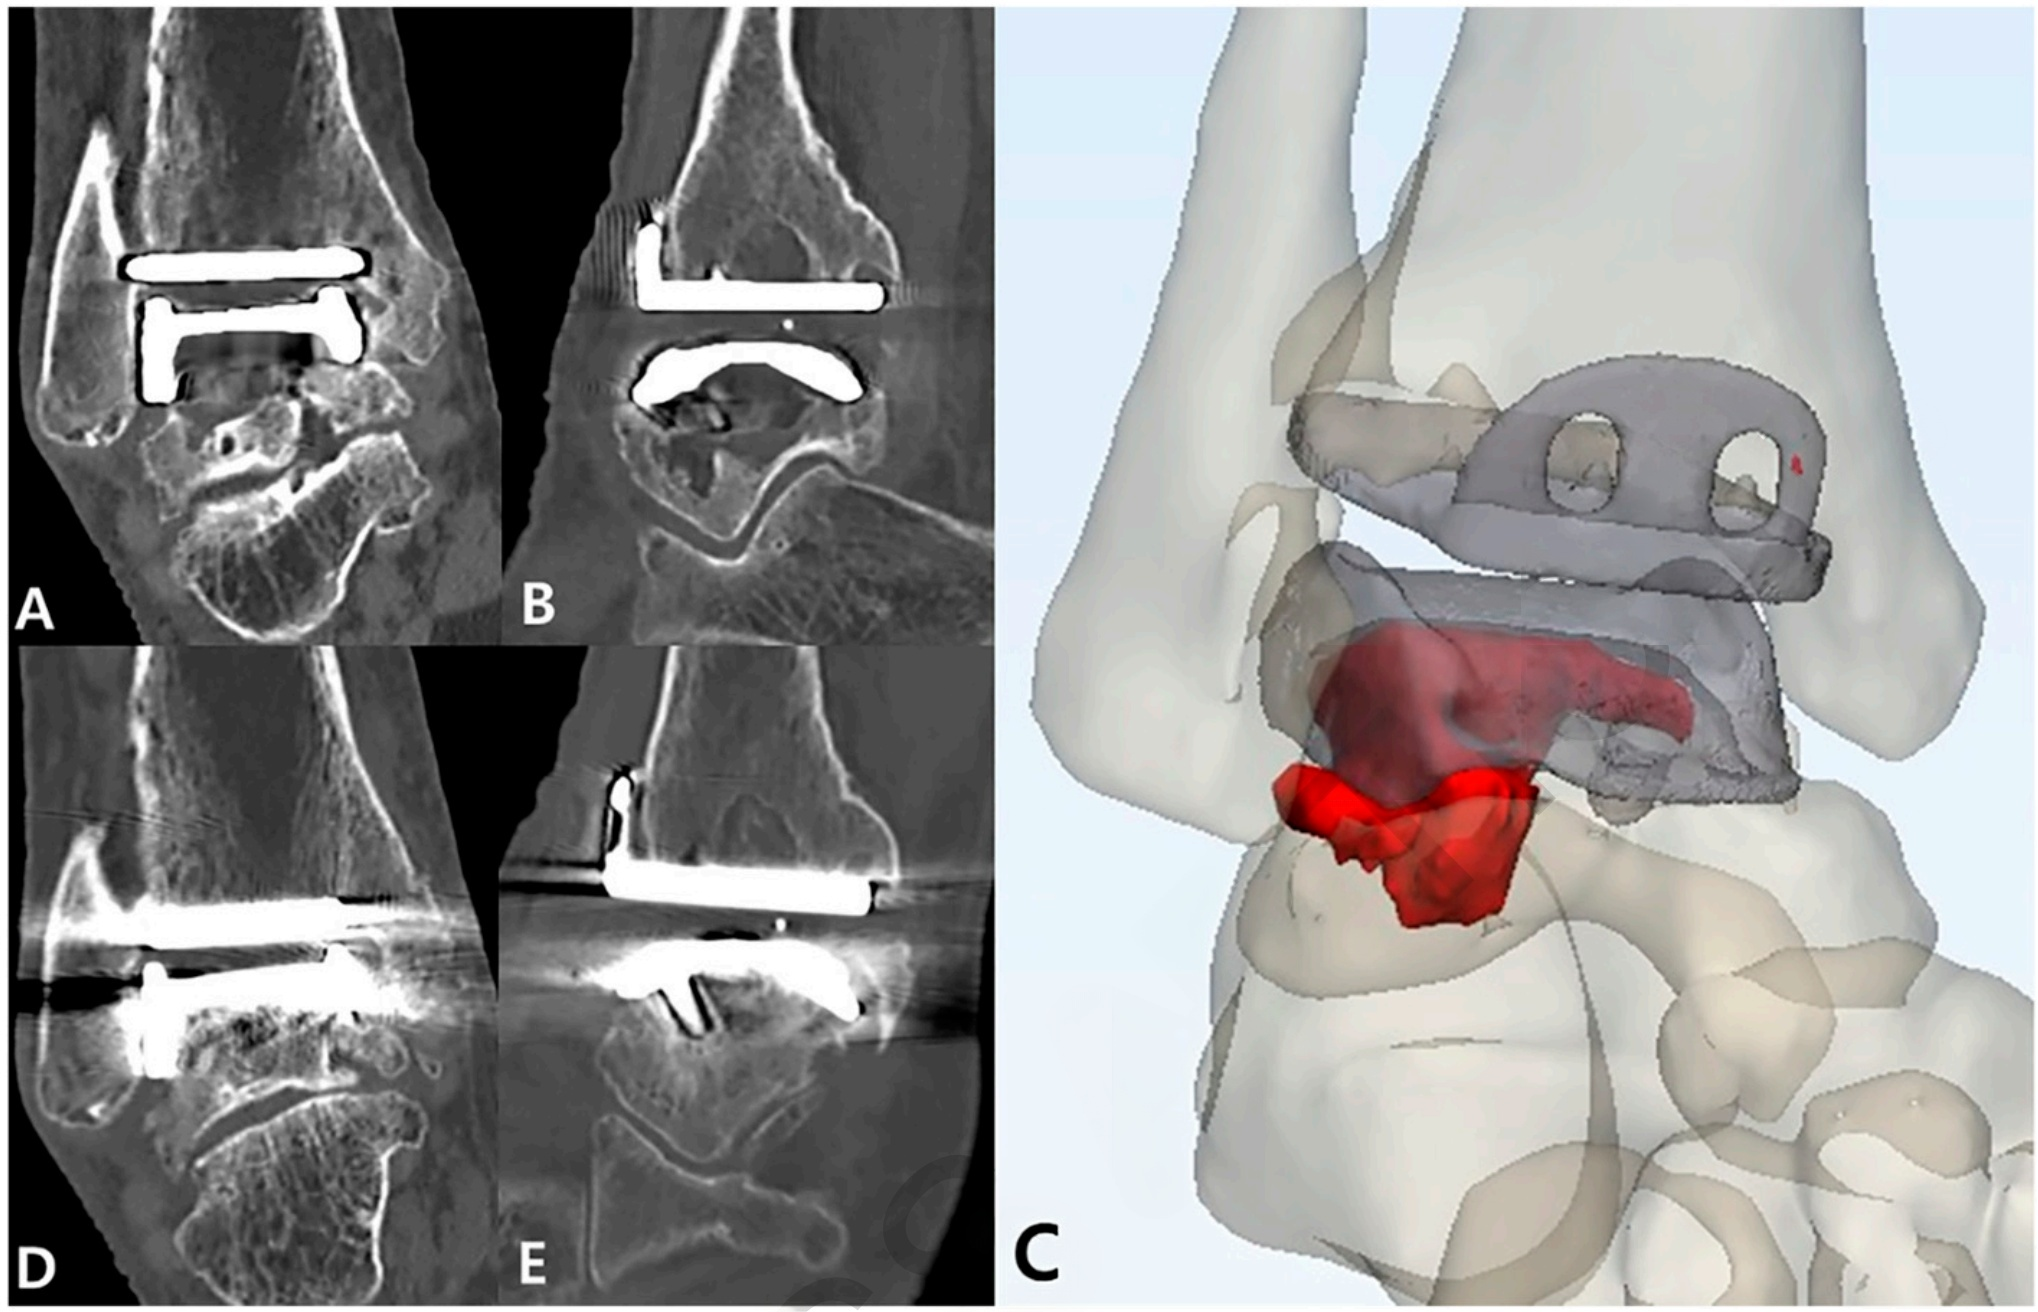

通过术前和术后至少2年的CT扫描,研究团队能够精确测量骨溶解囊肿的体积变化,同时评估假体的稳定性、骨移植的整合情况以及并发症发生率。

2. 囊肿体积显著减小但未消除

术前平均囊肿体积为4.8立方厘米,术后2年降至0.8立方厘米。然而,在长期随访中,41.7%的患者出现了新发囊肿,25.0%的患者出现原有囊肿复发。